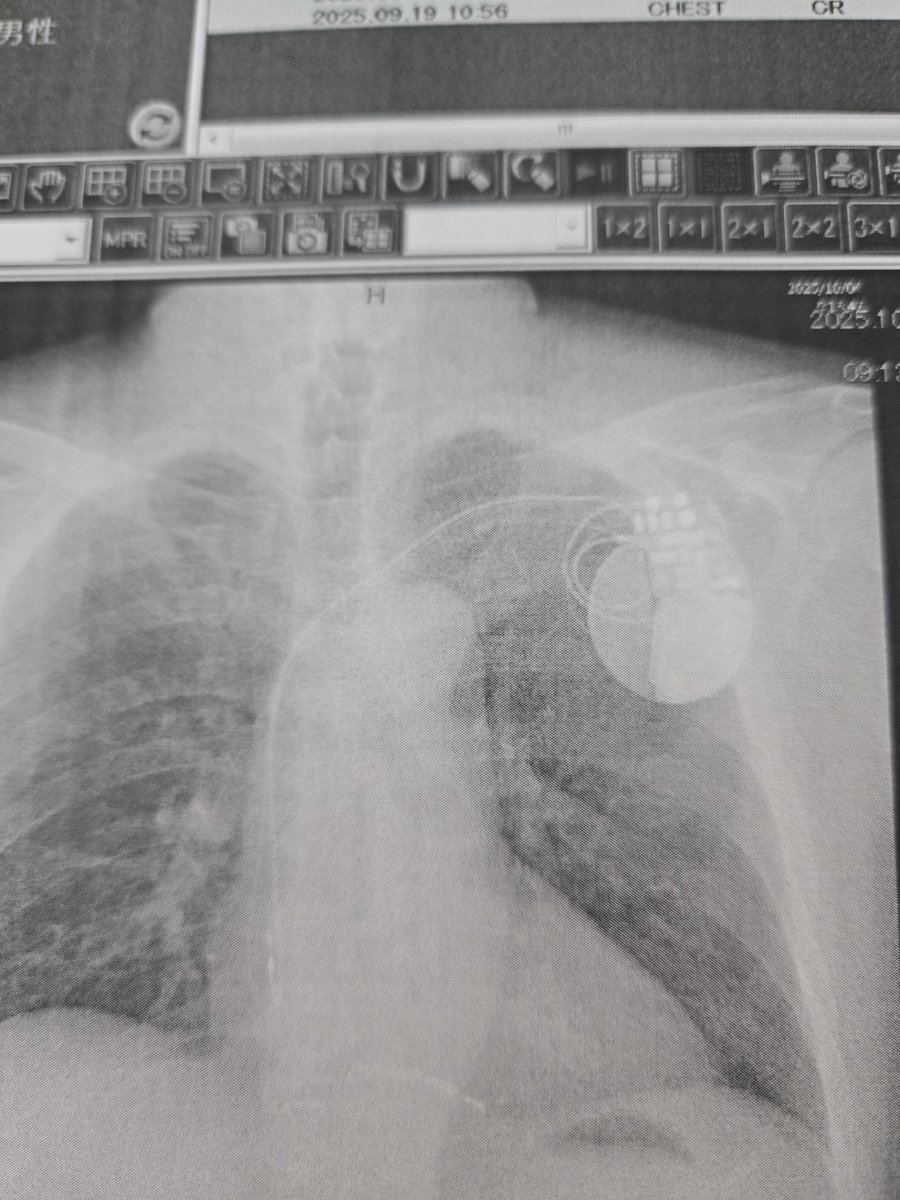

9/19に倒れ電車内&駅構内で声かけてくださった方や救急隊の方病院の主治医&看護師の方医専の研修の学生さん&教師の方、フォロワーさん術後リハビリして歩けるようになり今日無事退院します😢色々心配かけてすんませんでした&本当に感謝しかありません🙏🏻✨ #いつもRPイイね泣けるリプありがと #ICD

charandken's tweet image. 9/19に倒れ電車内&駅構内で声かけてくださった方や救急隊の方病院の主治医&看護師の方医専の研修の学生さん&教師の方、フォロワーさん術後リハビリして歩けるようになり今日無事退院します😢色々心配かけてすんませんでした&本当に感謝しかありません🙏🏻✨

#いつもRPイイね泣けるリプありがと

#ICD